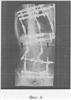

Фиг.4 – копия рентгенограммы после коррекции.